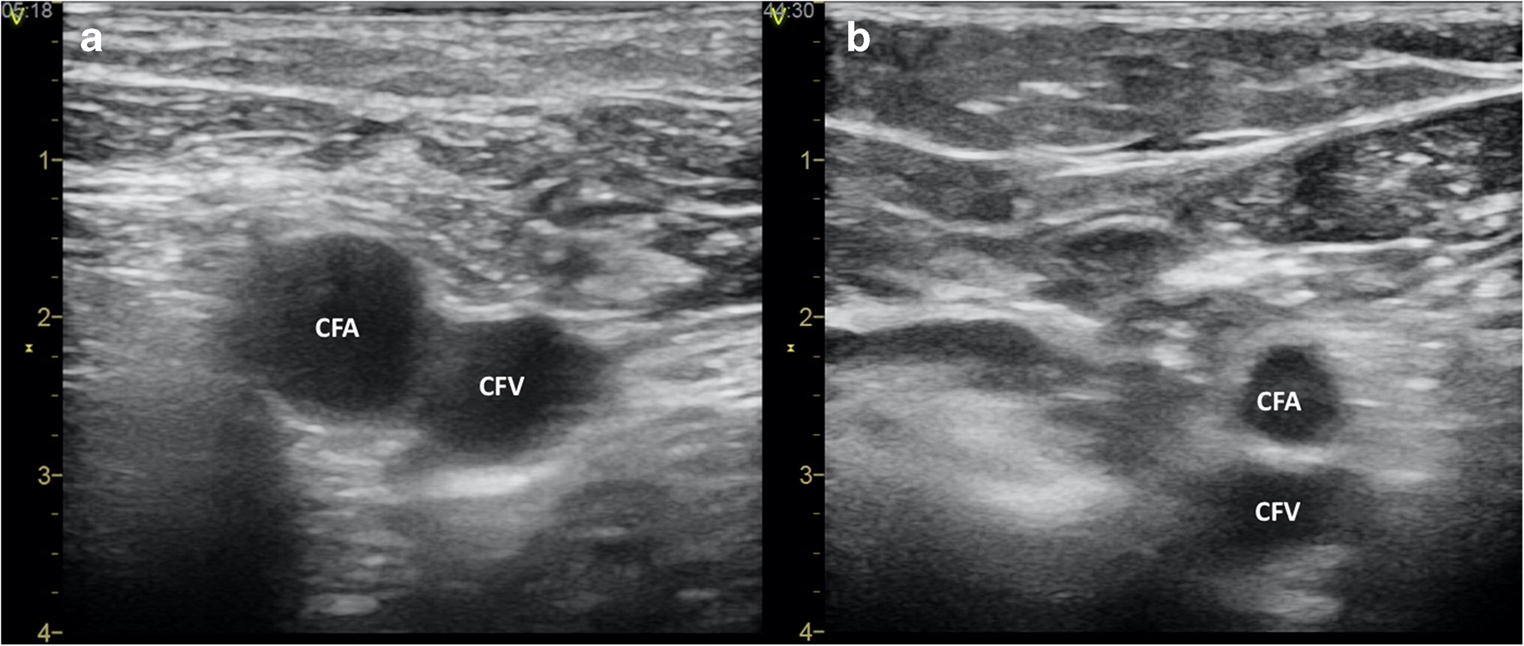

Supplementing the traditional anatomy landmark-based vascular puncture, an ultrasound (US) guidance offers potential benefits including prevention of vascular access-related complications. Using an US-gel-filled sterile sleeve covered vascular probe connected to a portable ultrasonograph allows direct and real-time visualization of the inguinal region. US may clarify the anatomy of the femoral vessels and the surrounding structures and identify variations that may interfere with the success of the puncture (Fig. 1). In addition, placing the probe perpendicular over the inguinal region and the femoral vein, it is possible to follow the needle during the puncture to guide and correct its course [7]. US-guided femoral puncture has a short learning curve and does not interfere with the normal workflow of EP procedures [7]. Earlier studies reported a lower rate of inadvertent arterial puncture, a higher rate of first-pass success, and a decreased risk of complications associated with the use of US [810].

Illustrative examples of two-dimensional ultrasound images of the femoral vessels with expected (Panel a) and unexpected (Panel b) localization. CFA common femoral artery, CFV common femoral vein